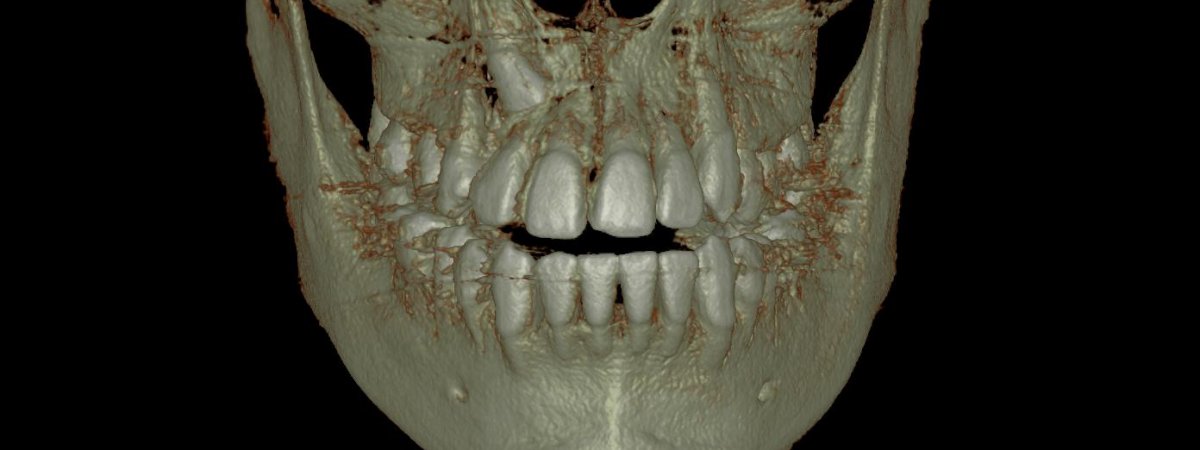

- Tomografía

- Implantes

- Localización de Diente Impactado

- Área Patológica